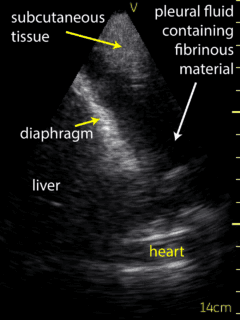

Ultrasound of the lung bases was conducted to assess for effusion by the consultant Respirologist using a Vscan device. There was no fluid present in the patient’s right pleural space. A moderate sized pleural effusion (Figure 1) was seen on the left side. The ultrasound of the left lung based was used to guide the thoracentesis (Video 1). The site of catheter insertion was landmarked at the 8th intercostal space, roughly 10 cm from the spine. Lidocaine was used to anesthetize down to the pleura. The catheter was introduced along the same location and angle, and a total 1.5 litres of serosanguinous fluid was collected. The procedure was well tolerated without complications.  Ultrasound following the procedure showed a very small amount of remaining fluid. Sliding lung/pleura could be seen as well. The patient experienced relief of symptoms following the procedure.